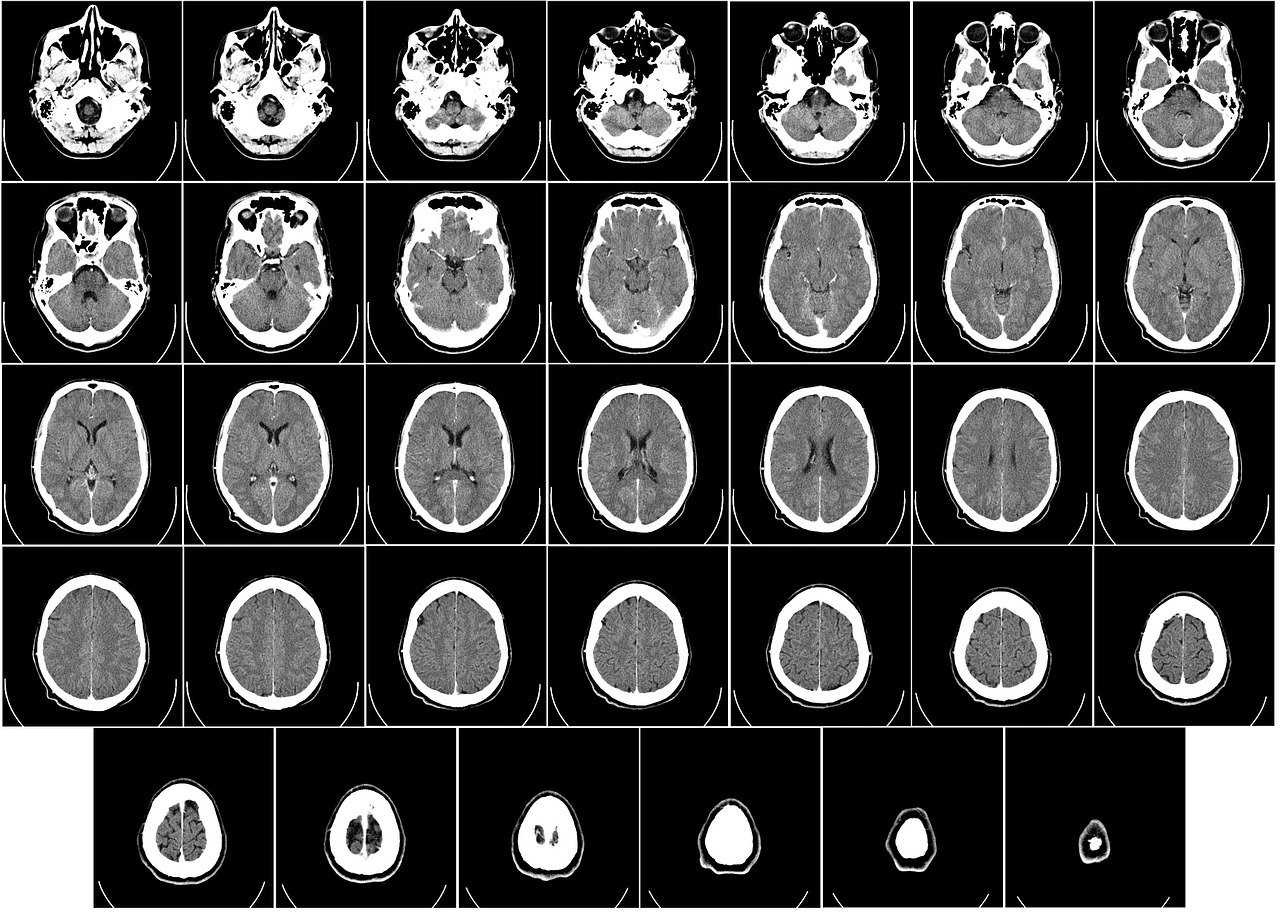

Brain CT Scan

Are you interested in having your brain CT Scan read?

Having your CT read allows you to know exactly what is going on when you are dealing with a difficult situation such as physical symptoms or any recurring symptoms.

A doctor will explain where in your brain the Hamer Foci are located and which Biological Programs are active for you

Indicate approximately how long they have been present

Clarify which phase they are in, and

Discuss possible solutions, focusing on your priority issue